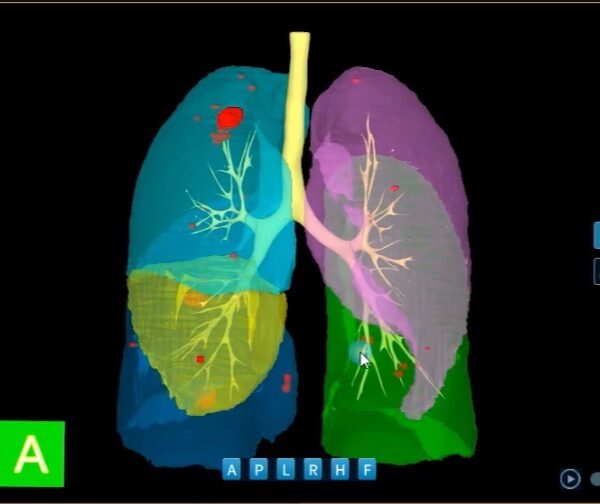

Análisis de Nódulos Pulmonares con IntelliAtlas Pro

Análisis de Nódulos Pulmonares con IntelliAtlas Pro: Detección precisa, seguimiento inteligente LLM Radiologia Análisis de Nódulos Pulmonares con…

Análisis de Nódulos Pulmonares con IntelliAtlas Pro: Detección precisa, seguimiento inteligente LLM Radiologia Análisis de…